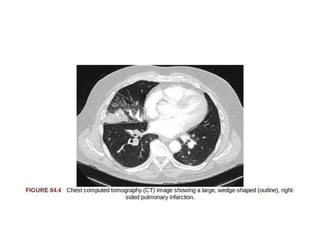

Pulmonary Infarction

• Pulmonary infarction is characterized by pleuritic chest pain

that may be unremitting or may wax and wane.

• Hemoptysis occasionally accompanies the pleurisy.

• The embolus typically lodges in the peripheral pulmonary

arterial tree, near the pleura.

• Tissue infarction usually occurs 3 to 7 days after embolism.

• Signs and symptoms often include fever, leukocytosis,

elevated erythrocyte sedimentation rate,and radiologic

evidence of infarction.